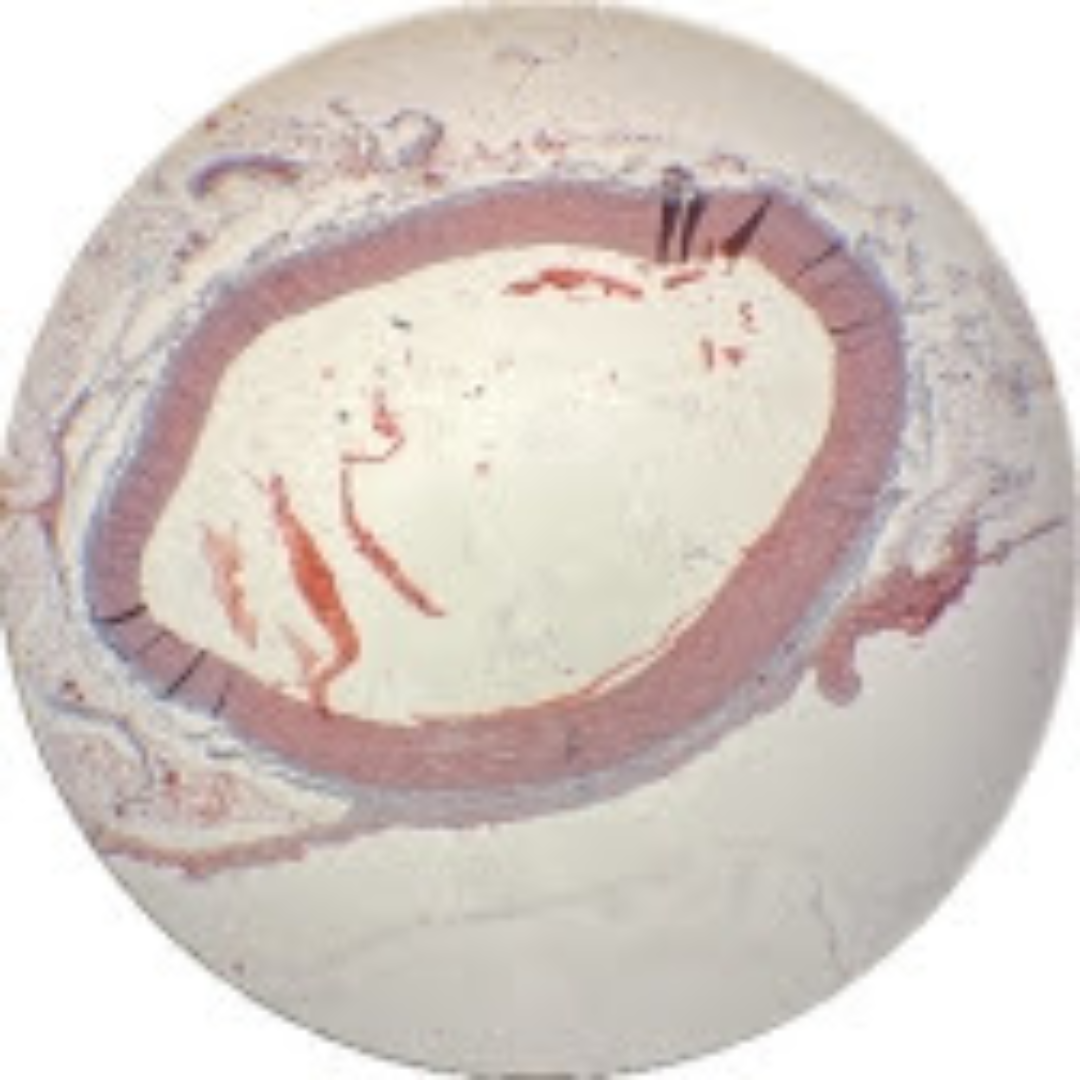

Muscular Arteries (Medium Sized Arteries)

Muscular Arteries (Medium Sized Arteries)

Muscular Arteries (Medium Sized Arteries)

Elastic Arteries (Aorta)

Elastic Arteries (Aorta)

Elastic Arteries (Aorta)